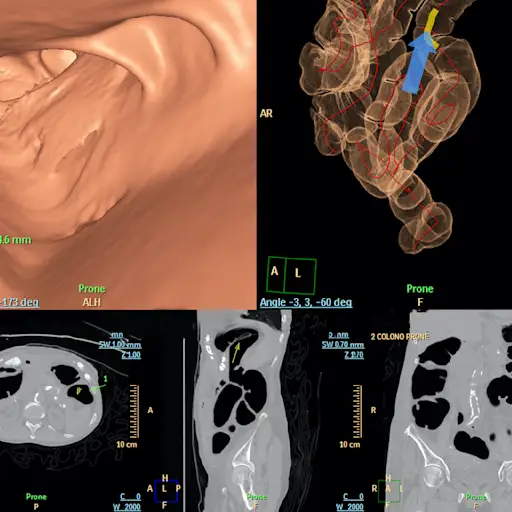

CT结肠镜

CT结肠镜,也被称为虚拟结肠镜,包括使用CT扫描来寻找结肠中的息肉。它也需要肠道准备,但不需要麻醉。阿尔博博士说:“它很擅长发现肿瘤,但在发现小肿瘤和息肉方面就不那么擅长了。”伊萨卡博士指出,在发现高风险息肉方面,结肠镜检查比CT结肠镜检查好五倍。如果结果正常,这个手术需要每五年重复一次。如果发现任何异常,你就需要做结肠镜检查来切除它。